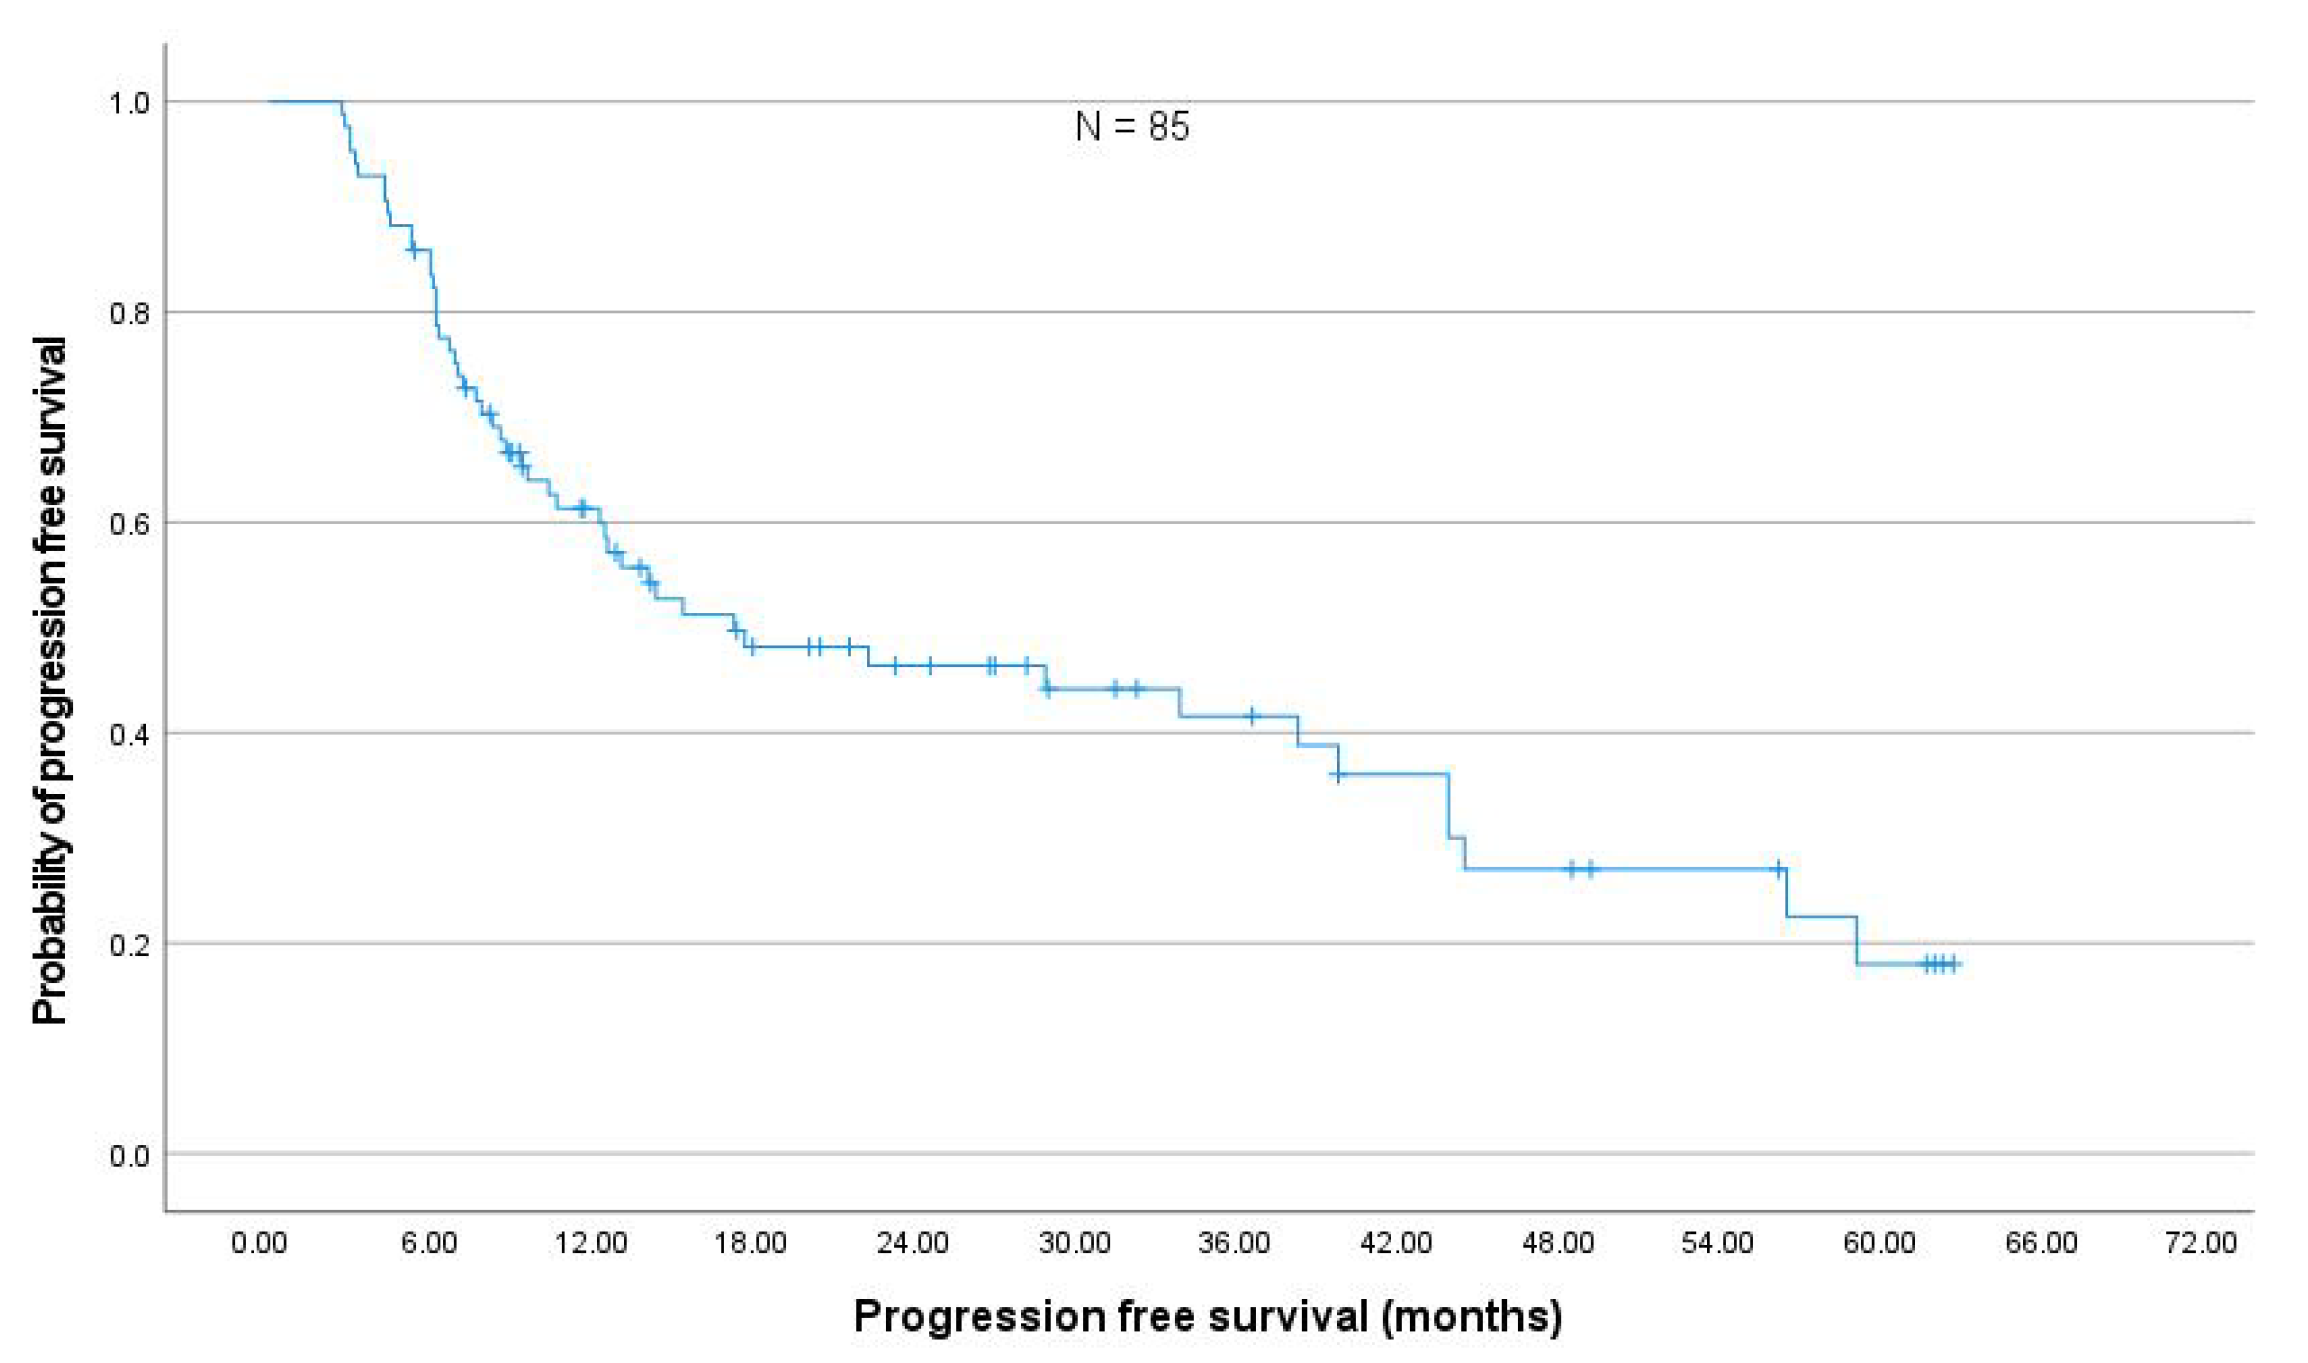

3.4. Toxicity